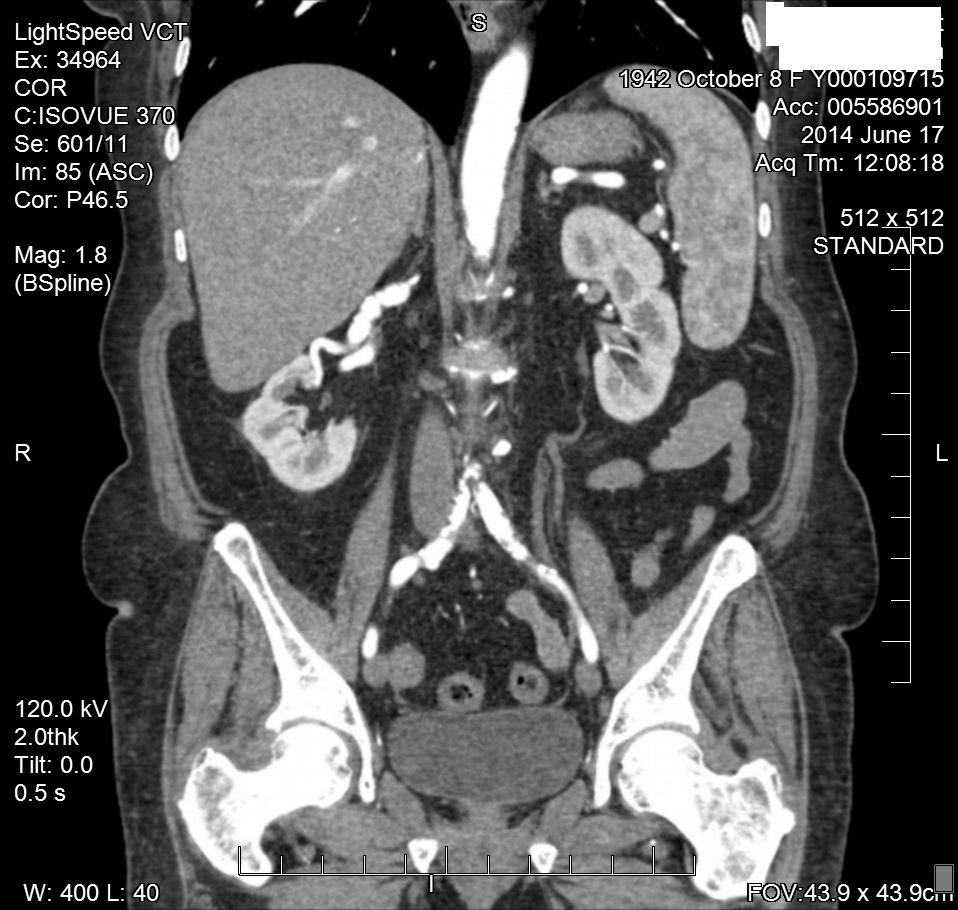

Figure 4 CTA of RRA FMD.

Two months later, the patient was referred to the radiology department for additional imaging with CTA. The CTA of the abdomen verified the “banded” appearance of both renal arteries consistent with FMH. The CTA also verified the angiographic findings of a right renal artery helium AV fistula or AV malformation. Since the bilateral renal artery angioplasties, the patient’s blood pressures have remained in the 130/70mm Hg range (Figure 7-9).